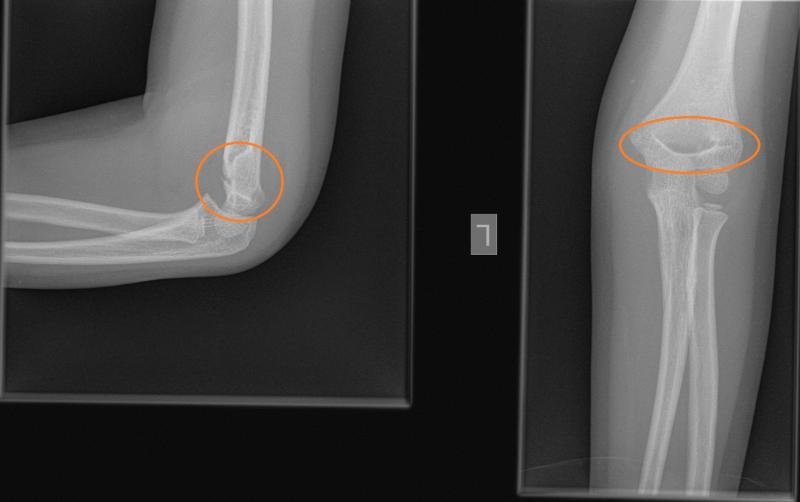

Przypadek 2: 5-letnia dziewczynka po upadku z hulajnogi. Obrzęk i bolesność lewego stawu łokciowego.

Rozpoznanie: Złamanie nadkłykciowe lewej kości ramiennej.